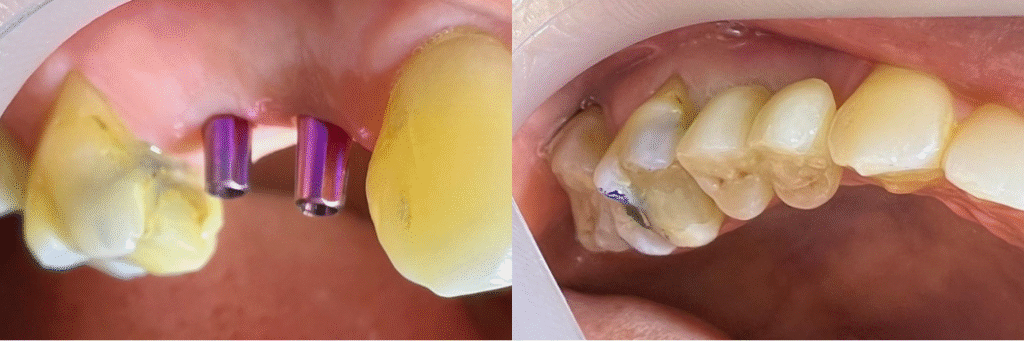

Implantes + coronas

A small river named Duden flows by their place and supplies it with the necessary regelialia. It is a paradisematic country, in which roasted parts of sentences fly into your mouth. Even the all-powerful Pointing has no control about the blind texts it is an almost orthographic life

One day however a small line of blind text by the name of Lorem Ipsum decided to leave for the far World of Grammar. The Big Oxmox advised her not to do so, because